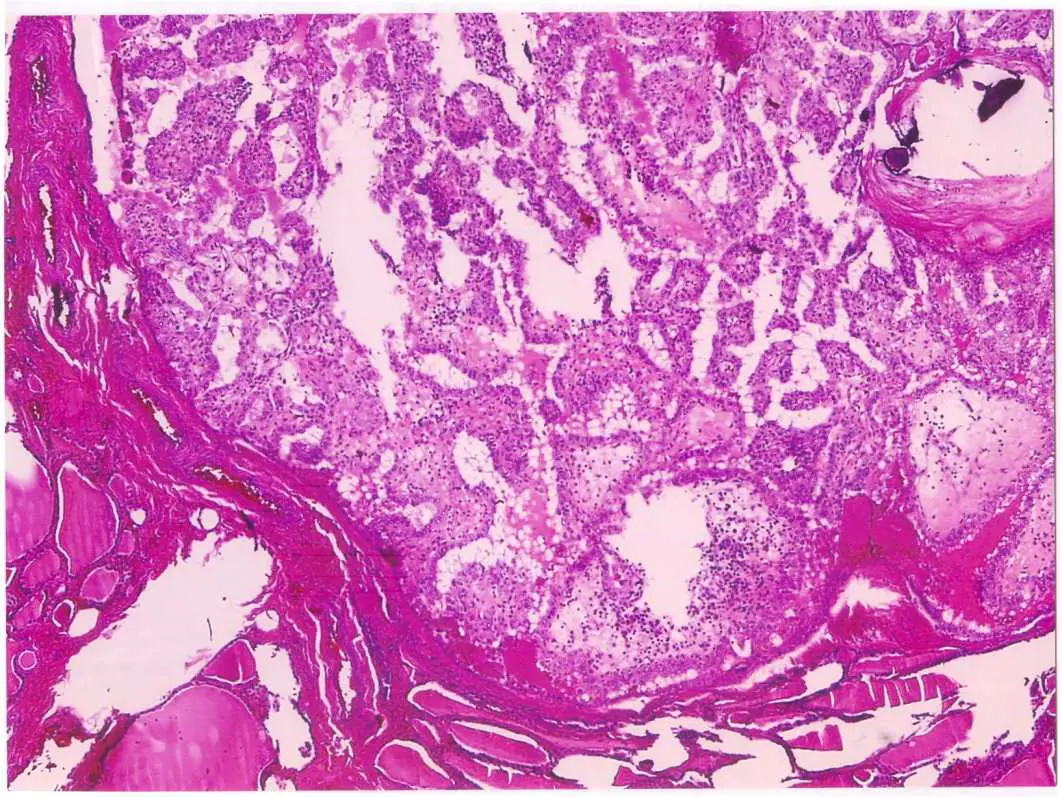

圖示為50 歲女性甲狀腺腫瘤之病理切片。下列敘述何者最不符合此腫瘤的臨床或病理特徵?

本切片為 H&E 染色的甲狀腺腫瘤病理切片,低倍鏡下可見腫瘤組織呈乳突狀(papillary)構造,乳突狀突起由纖維血管核心(fibrovascular core)構成,表面覆蓋單層至複層腫瘤細胞。腫瘤細胞排列緊密,細胞核特徵符合乳突性甲狀腺癌的典型表現。切片中可見乳突狀葉片(papillary fronds)廣泛分布,同時可見部分膠質(colloid)存在。整體病理型態最符合乳突性甲狀腺癌(PTC)的組織學診斷。高倍鏡下可預期見到典型的細胞核特徵,包括:核溝(nuclear grooving)、核假性包涵體(nuclear pseudoinclusion)、及「Orphan Annie eye」核(核染色質清澈,如毛玻璃樣)。